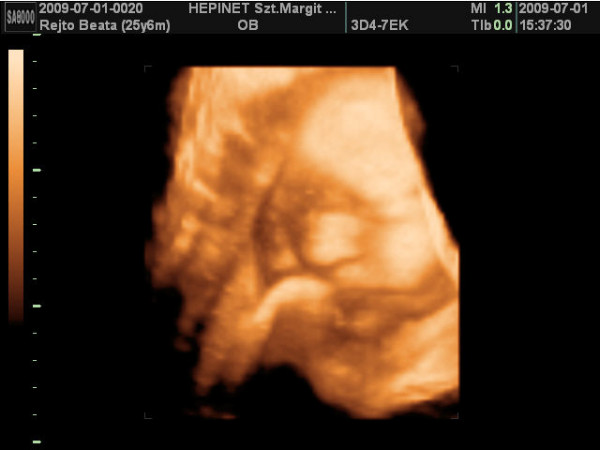

ma vagyok 6 hetes 5 napos.a jó hír,hogy szombaton már láttam és hallottam életemben először a kicsi szívhangját!!!!!!![]()